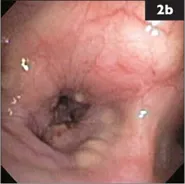

2 A 13-year-old neutered male Shih Tzu has been coughing for the past 3 weeks, after he was at a boarding facility for several weeks. Decreased appetite and weight loss were noted recently. Amoxicillin with clavulanate and hydrocodone were prescribed elsewhere for suspected bronchitis, but the owner has had trouble administering the medication. The dog is quiet, but alert and responsive. Body temperature, HR, and respiratory rate are normal. Soft pulmonary crackles are heard over the left hemithorax. Tracheal palpation elicits a non-productive cough. The rest of the physical examination is normal. Chest radiographs show a moderate to severe bronchointerstitial pattern in the caudal lung with alveolar infiltrates in the right cranial lobe. Cardiac size and pulmonary vasculature are normal. A hemogram shows mild thrombocytosis, but is otherwise normal; serum chemistries and urinalysis are unremarkable. Bronchoscopy (2a, b) and BAL are performed.

i. What findings are shown in the bronchoscopic images?

2 i. The airways appear diffusely edematous with mild erythema consistent with generalized bronchial inflammation. Small yellowish tan nodules are seen on some surfaces (2b, from right cranial bronchus).

ii. The radiographic pattern suggests pneumonia or an infiltrative inflammatory or neoplastic disease. Given the history of boarding, infectious tracheobronchitis with secondary pneumonia is a consideration. Small nodules within the airways most often result from chronic inflammation and mucosal proliferation secondary to chronic bronchitis, but neoplastic infiltration is another consideration. Nodules found only near the carina may signal infection with the parasite Oslerus osleri in endemic areas. This dog’s systemic signs, along with the relatively recent onset of coughing, are not typical for chronic bronchitis.

iii. In addition to BAL cytologic analysis and culture, airway brushings and pinch biopsy of a nodule should be obtained during the bronchoscopic procedure. If evaluation of these samples does not yield a definitive diagnosis, lung biopsy is recommended. In this dog, cytologic evaluation revealed mild purulent inflammation, mild chronic hemorrhage, and variably-sized cohesive clusters of highly vacuolated cells thought to be carcinoma cells. BAL cultures yielded no aerobic or anaerobic growth.